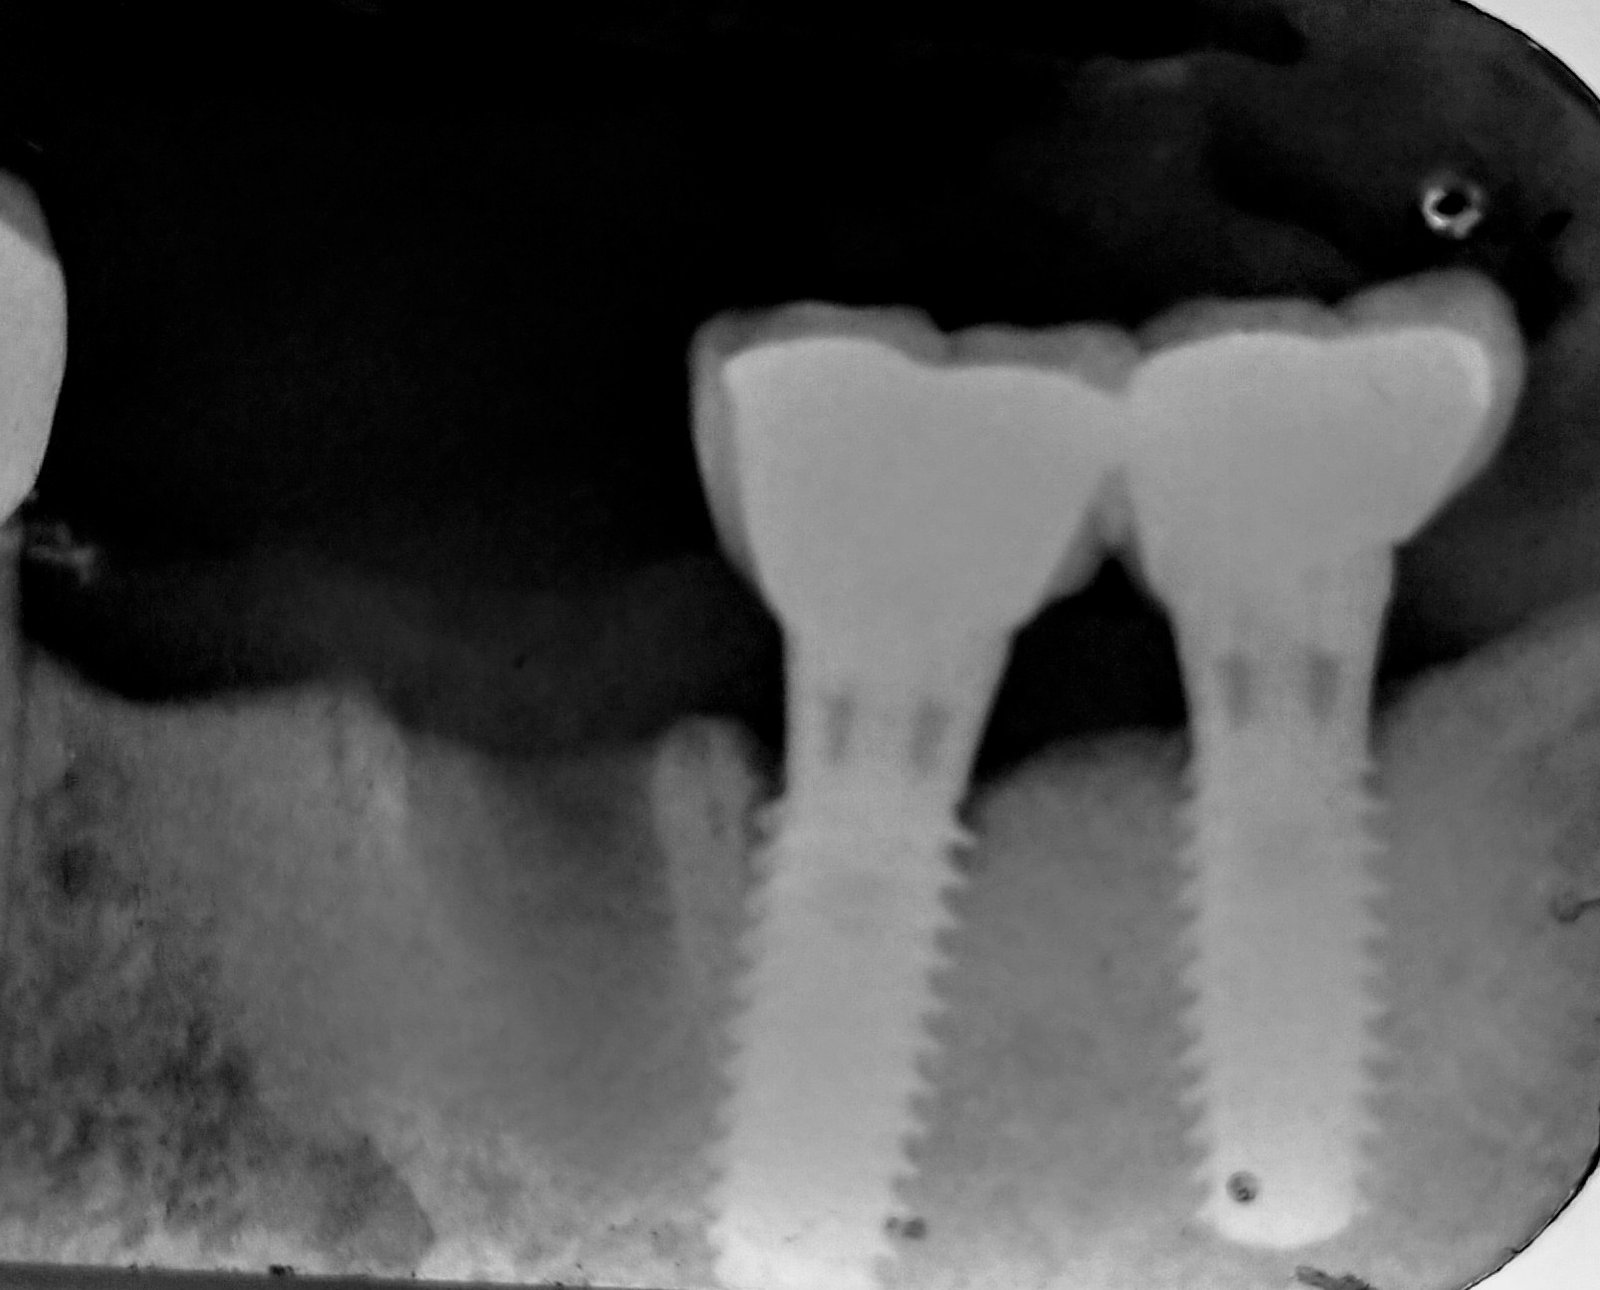

Buscando Conexión y Compatibilidad de dos implantes.

Buenas tardes!! tengo un caso que necesito restaurar pero no logro identificar bien los implantes se que es una conexión octagonal pero no se con que sea compatible , los [...]